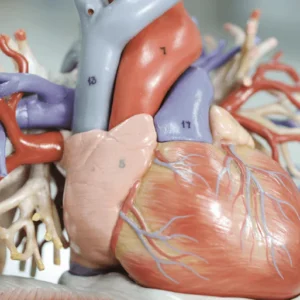

Teach children about the human circulatory system and heart health in our pre-planned science project, Blood Heart. This Year 6 project and supporting resources develop children’s knowledge about the workings of the heart and significant medical discoveries.

This project teaches children about the transport role of the human circulatory system, its main parts and their primary functions. They learn about healthy lifestyle choices and the effects of harmful substances on the body.